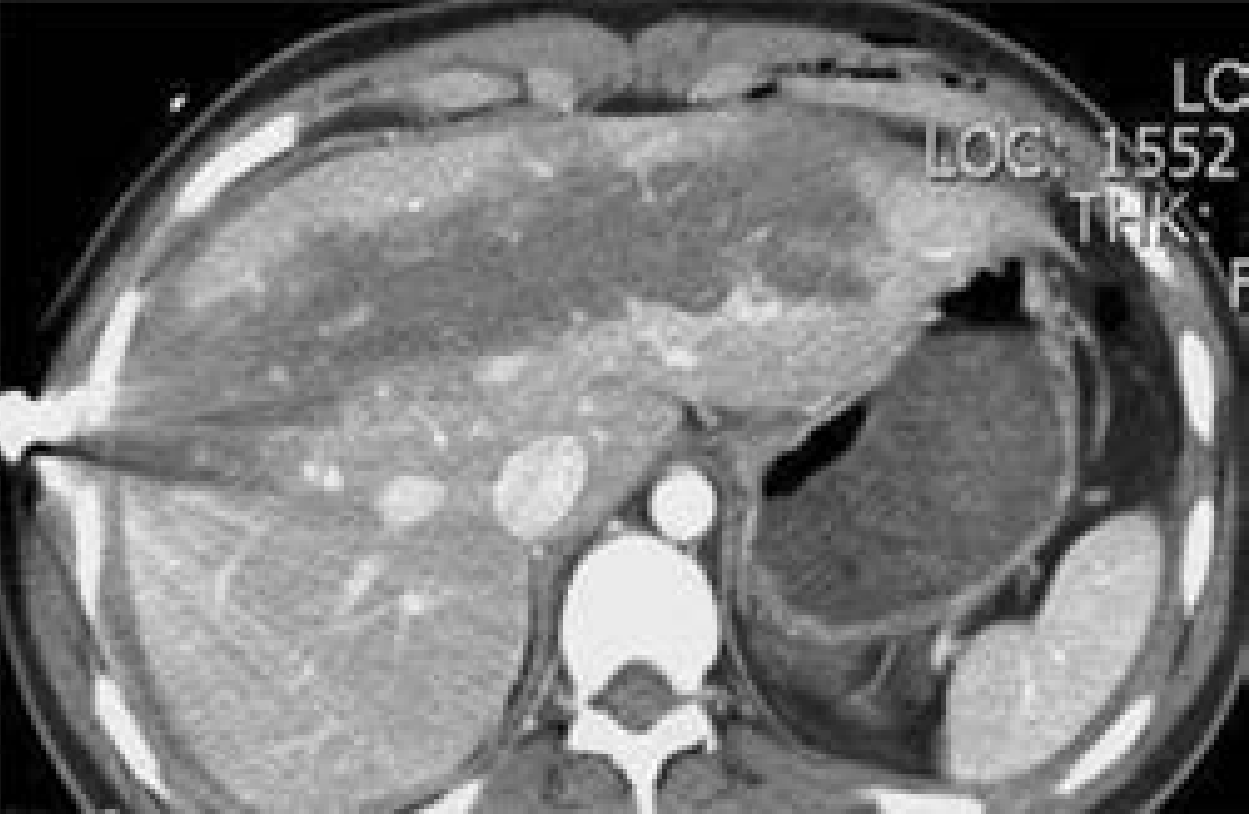

CT images of liver injury:

CT of liver injury grades

CT liver injury

CT images of liver injury — Current Surgical Therapy 14e, p. 1342